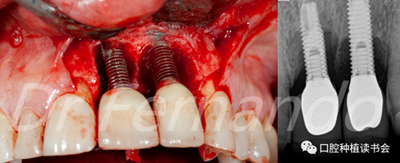

圖4 前牙美學(xué)區(qū)種植體周圍炎采用手術(shù)&骨再生治療

盡管手術(shù)治療似乎能改善結(jié)果;但只有將手術(shù)治療和骨再生相結(jié)合才能獲得更高的成功率。Schwarz等人發(fā)現(xiàn)這種再生手術(shù)治療有2年以上的滿意效果,能使種植體周圍的骨吸收停止,探診出血率由80%降至34%(圖5 )。

圖5通過手術(shù)治療,種植體周圍獲得骨再生,術(shù)后2年效果穩(wěn)定(圖2、圖4相同病例)